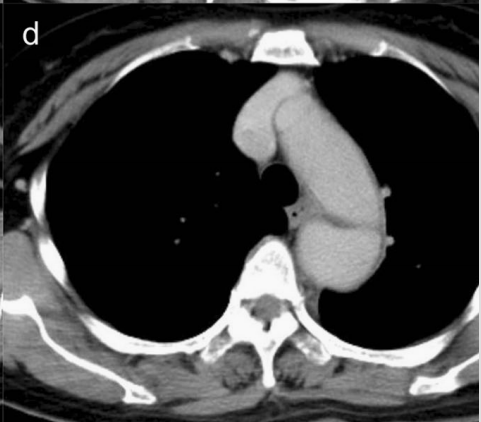

下图的胸部CT平扫,有什么大问题?

图4

仔细一看,主动脉里面有线样高密度阴影!这个要高度警惕主动脉夹层!